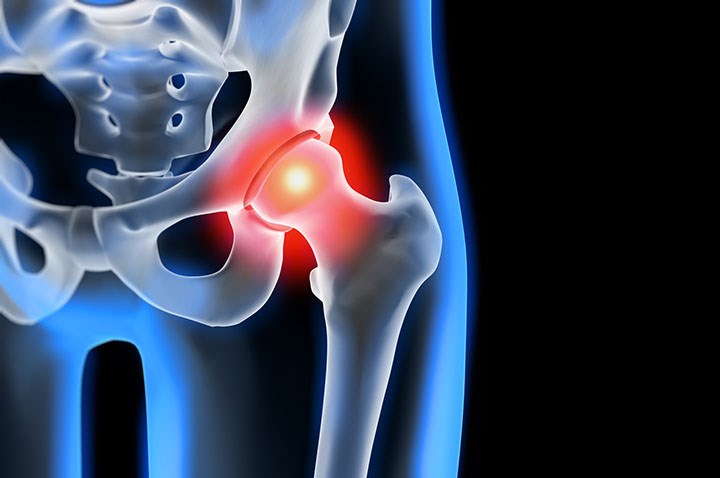

• Femoroacetabular Impingement

Femoroacetabular Impingement

Hip joint pain is no longer exclusive to older individuals with sedentary lifestyles. Increasingly, individuals aged 30-40, and sometimes even younger, leading active lifestyles are visiting orthopedic clinics with this complaint. One potential cause of this pain, identified by orthopedic surgeons, radiologists, and physiotherapists, is femoroacetabular impingement (FAI). This condition is...